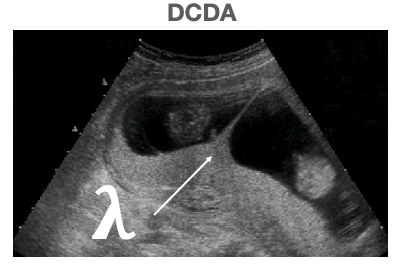

Q

What US sign is associated with dichorionic diamniotic twins?

A

lambda / twin peak sign

• this occurs as there is a membrane between the twins

• separation of the chorionic + amniotic sacs resembles a lambda

How well did you know this?